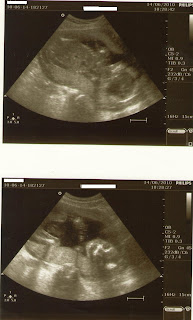

The baby has turned around and is no longer breech, hopefully it will stay that way. There are a couple of ultrasound pictures from yesterday that you might find entertaining. The kid looks like a pretzel. One foot and hand under its chin, the other leg straight down and bent at the knee and the other arm was straight down I think. We didn’t' get a good look at it.

Here are a couple of pictues from our 23 week ultrasound. The first one is kind of a wierd angle so I've included descriptions. We didn't get any good pictures at the 24 week photo session. Hopefully we will have more cooperation for week 26.